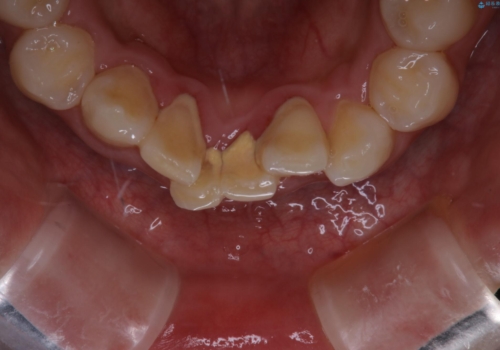

矯正を始めるのをきっかけにクリーニングを約5年ぶりに行ったそう。

プラークや歯石がとても多く付いていたので、すべて除去していきました。

長い間、歯石やプラークが付いていたため、歯茎が腫れて出血していますが、汚れを除去したことによってだんだんと腫れが引いてきます。再度、汚れが付かないようにホームケアを頑張ることがとても大切なため、ブラッシングの説明も細かくさせていただきました。